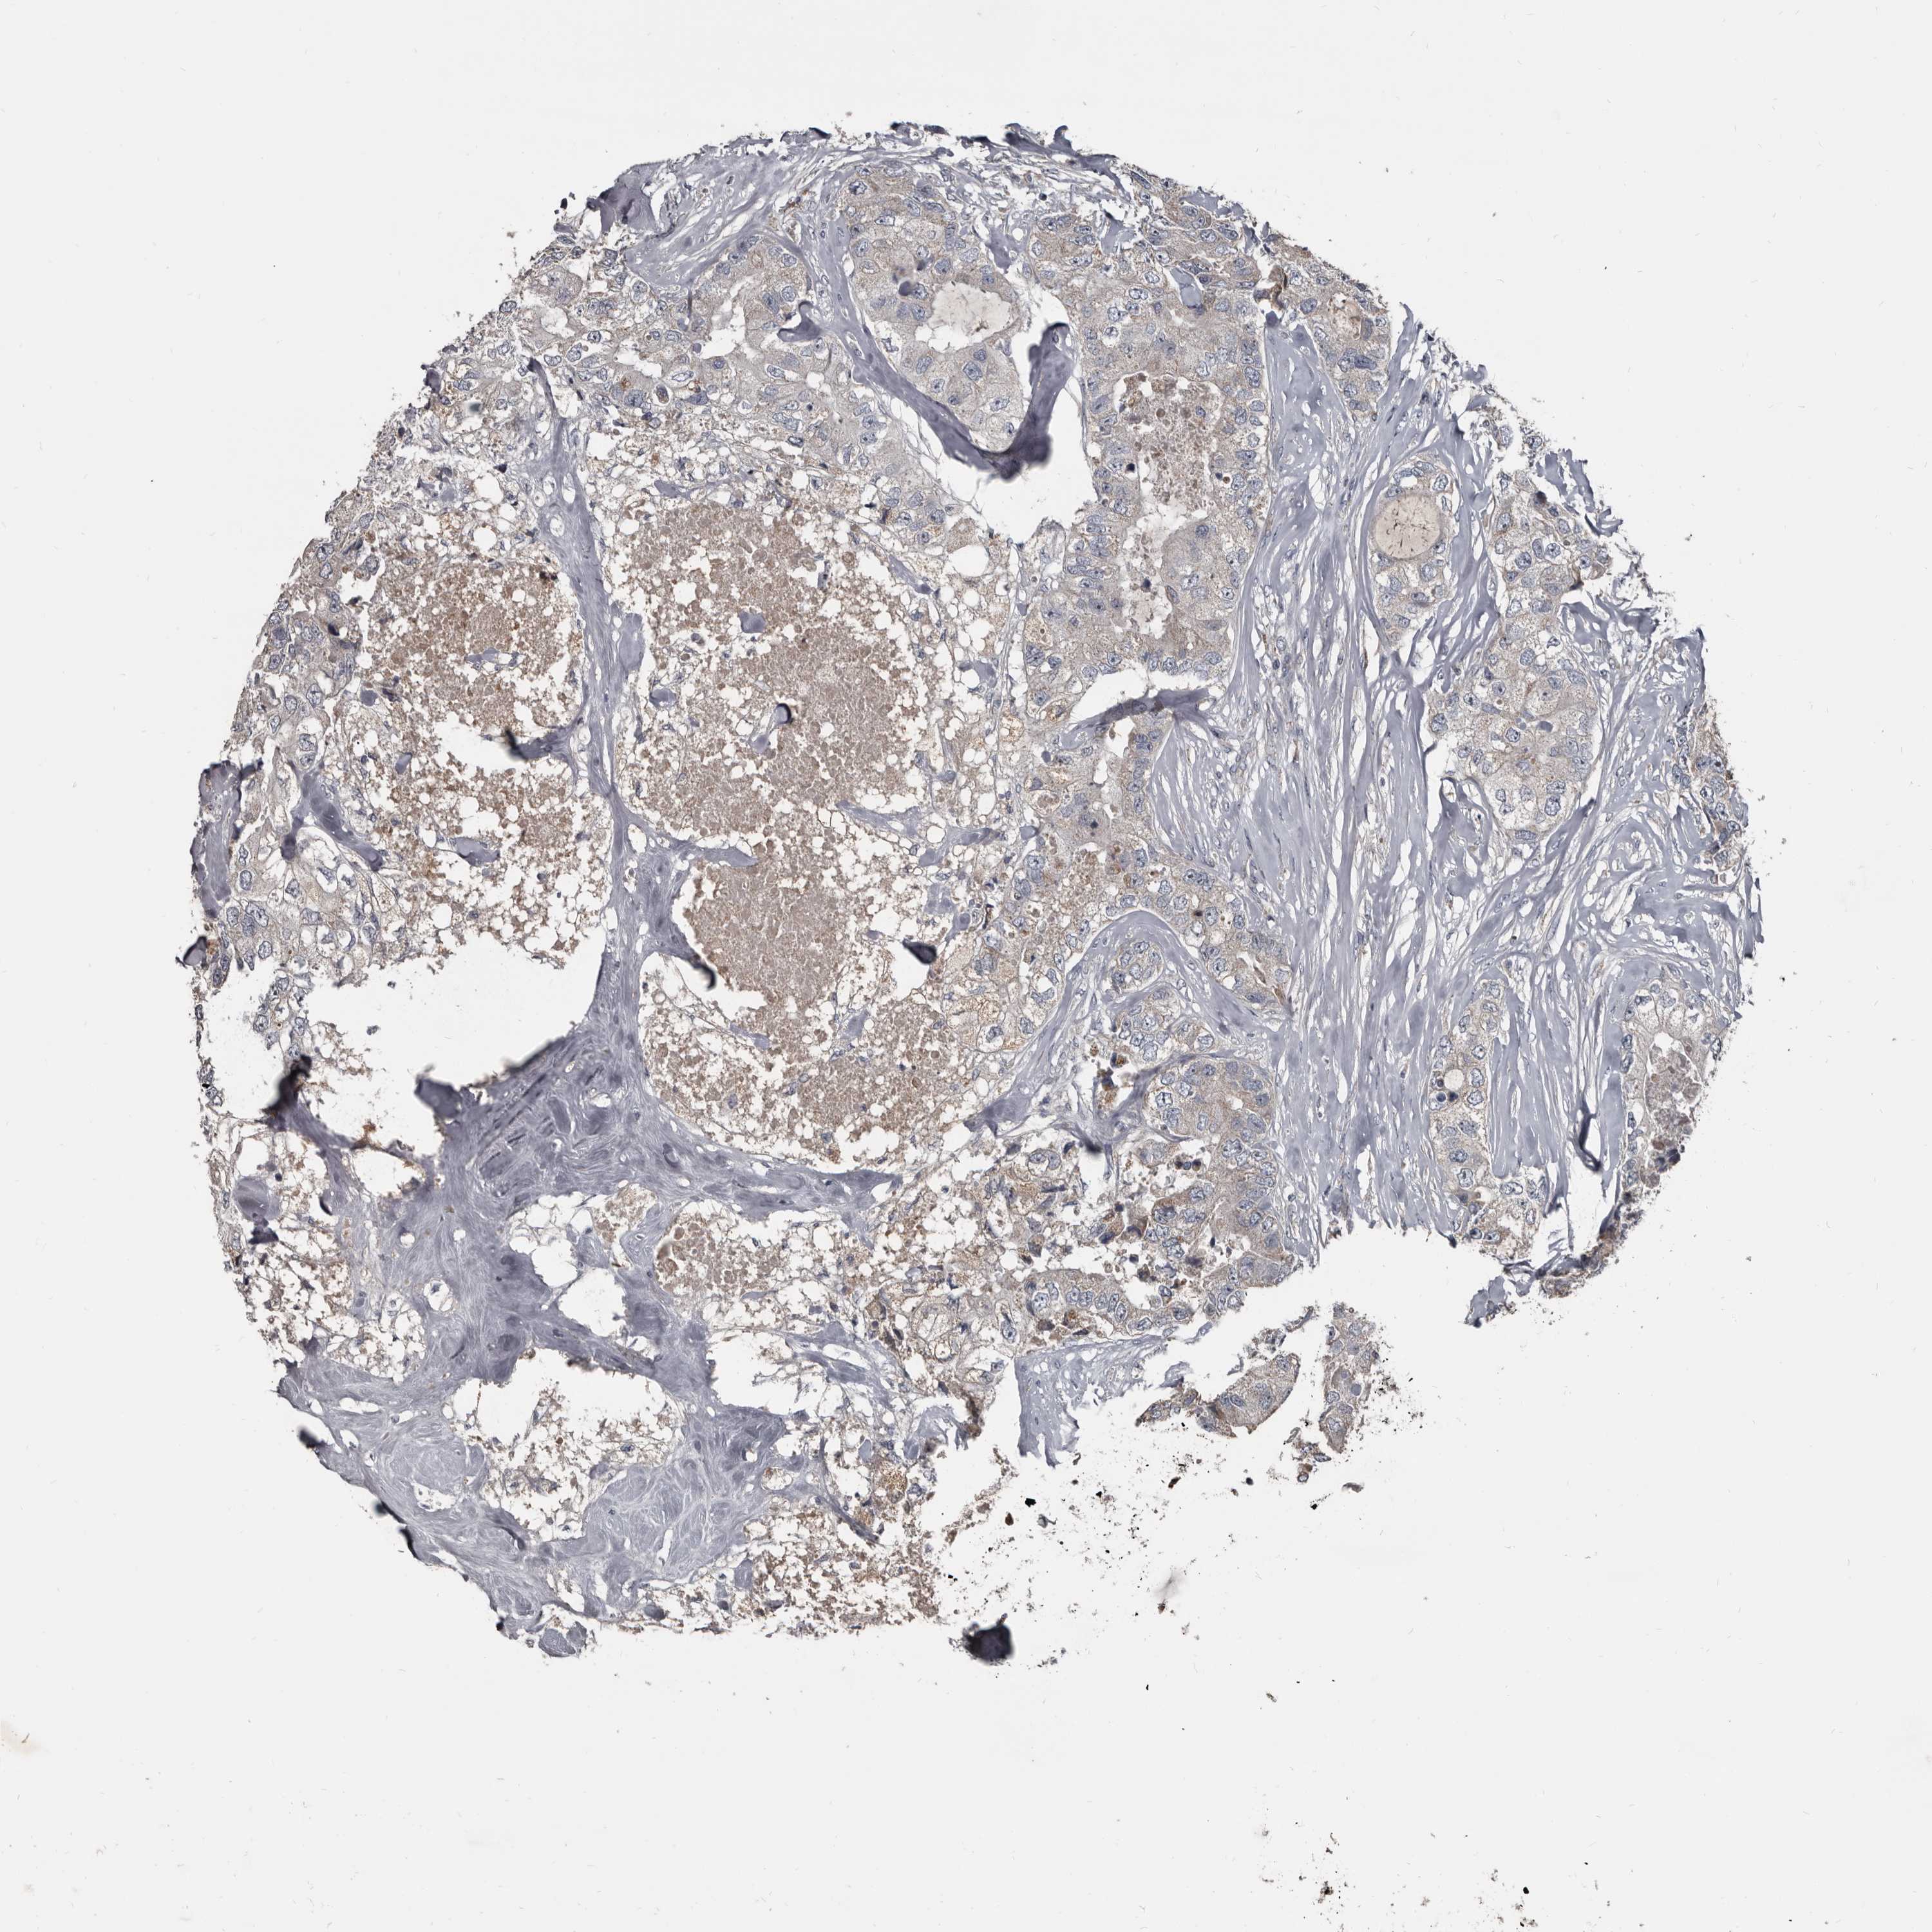

CANCER BREAST CANCER Show tissue menu

BRCA TCGA BRCA VALIDATION PROTEIN EXPRESSION